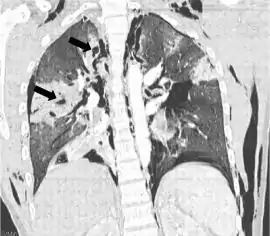

![]() مسح بالأشعة المقطعية الاكليلية يظهر فيها شفيف الأشعة (المناطق الباهتة في التصويرالشعاعي) في الرئة الناجمة عن تهتك الرئة على يسار الصورة.(الأسهم السوداء). تصنيف وموارد خارجية، تخصص طب الطوارئ. مسح بالأشعة المقطعية الاكليلية يظهر فيها شفيف الأشعة (المناطق الباهتة في التصويرالشعاعي) في الرئة الناجمة عن تهتك الرئة على يسار الصورة.(الأسهم السوداء). تصنيف وموارد خارجية، تخصص طب الطوارئ. | |